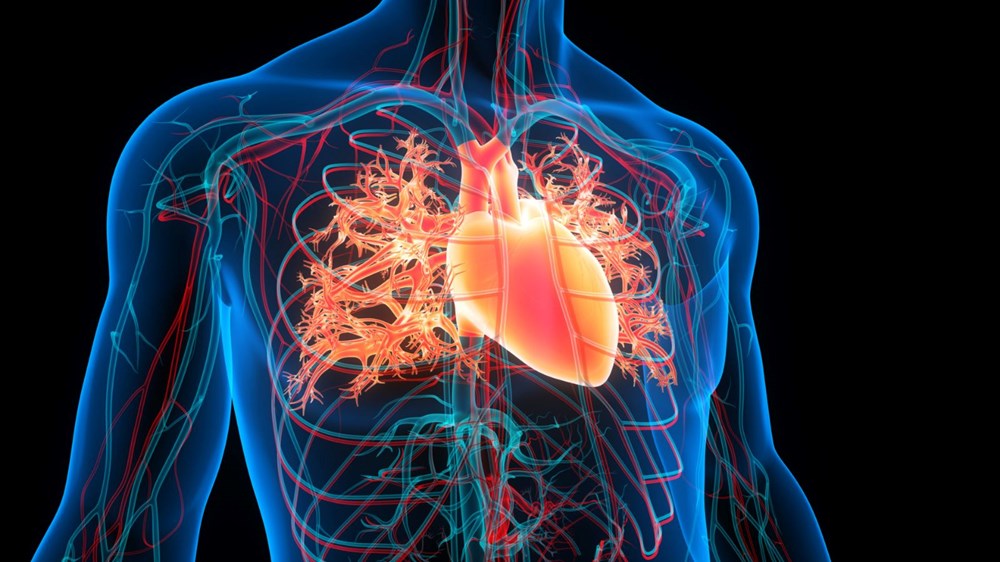

Hipertansiyon, dünya genelinde milyonlarca insanı etkileyen ve kalp-damar hastalıklarının en önemli risk faktörlerinden biri olarak öne çıkıyor. Uzmanlara göre, düzenli aerobik egzersiz yalnızca kan basıncını düşürmekle kalmıyor, kalbi güçlendirerek uzun vadeli koruma da sağlıyor.

Kardiyolog Dr. Jeremy London sosyal medya hesabı Instagram üzerinden paylaştığı videoda egzersizi günlük rutine dahil etmenin “kalp sağlığını korumanın ve kan basıncını kontrol altında tutmanın en güvenilir yolu” olduğunu belirtiyor.

Aerobik egzersiz, yalnızca kan basıncını dengelemekle kalmıyor. Kalp kasını güçlendiriyor, kan dolaşımını hızlandırıyor, “kötü” kolesterol (LDL) düzeyini düşürürken “iyi” kolesterolü (HDL) yükseltiyor. Ayrıca, kilo kontrolüne ve kan şekeri dengesine de katkı sağlıyor.

Bu etkiler birleştiğinde, kalp hastalığı, felç ve diğer kardiyovasküler sorunların riski azalıyor.